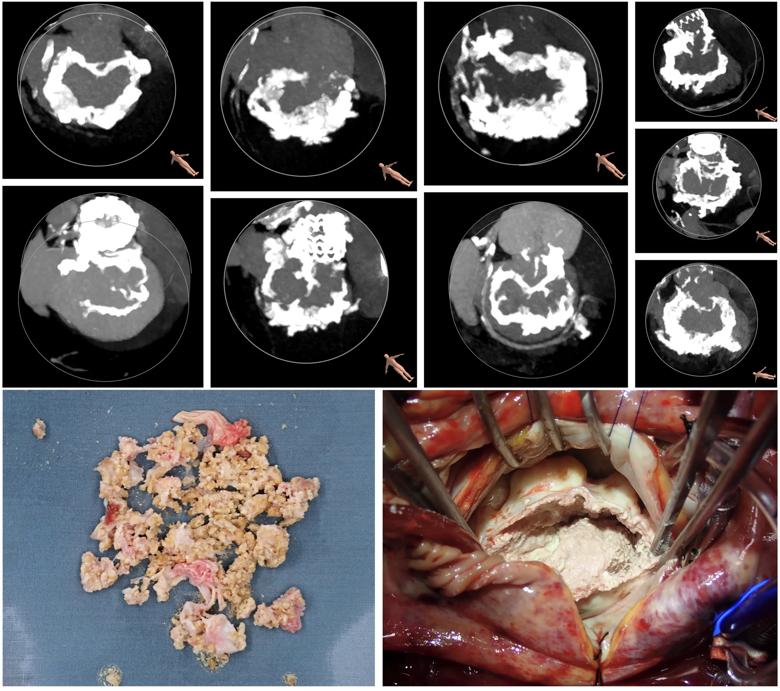

“MAC is highly variable, with different textures and distributions in relation to the annulus [Figure 1],” says Serge Harb, MD, a cardiologist in Cleveland Clinic’s Section of Cardiovascular Imaging who is at the forefront of advancing imaging techniques related to MAC. “Key CT considerations for surgical planning include delineating the distribution and extent of calcification, assessing regional calcium density (i.e., MAC mapping) and defining the proximity of the left circumflex artery to the MAC. For transcatheter therapies, CT further informs annular sizing to ensure appropriate device fit and helps evaluate the risks of left ventricular outflow tract [LVOT] obstruction and paravalvular leak.”

large grouping of heart scans and photos of heart valve calcification

Figure 1. Top rows depict the wide range of potential MAC distribution patterns on CT imaging. Bottom row shows the variation in potential MAC consistencies, from solid (left photo) to caseous (right photo).